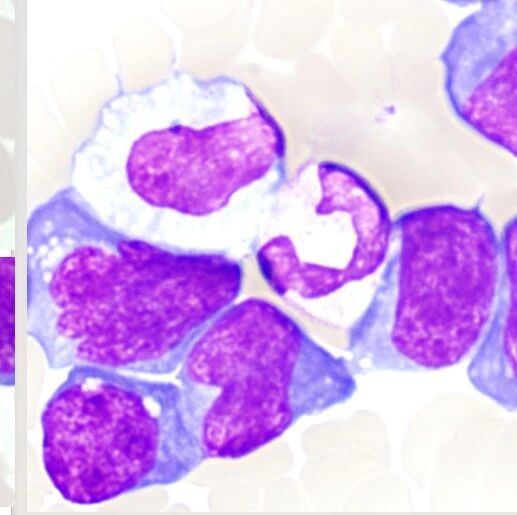

人多未必势众,黑手究竟是谁?以浆细胞增生为主要临床特征的淋巴结滤泡辅助T细胞淋巴瘤血管免疫母细胞型1例